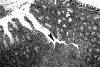

Figure 2.

Cryptabscesses (arrowheads) and loss of mucosal goblet cells in rectal mucosa of IL-10−/− mouse infected with E. faecalis for 10 weeks. H&E; original magnification, ×100.